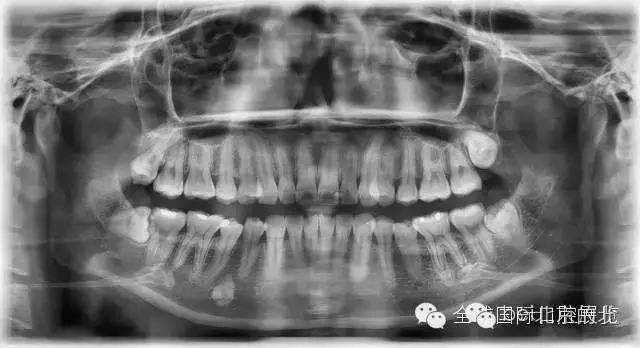

常規(guī)X-RAY全景片檢查

一個(gè)病人進(jìn)來(lái)我們不單單要關(guān)注患牙,而且要關(guān)注他們?nèi)诘难例X情況,卡瓦的跨學(xué)科病例大賽讓我更加重視了患者的全局觀,雖然患者暫時(shí)不一定會(huì)處理,但是作為我們醫(yī)生有必要告訴他們,選擇權(quán)交給患者自己,也希望和所有醫(yī)生共勉。

先看看患者別的情況: